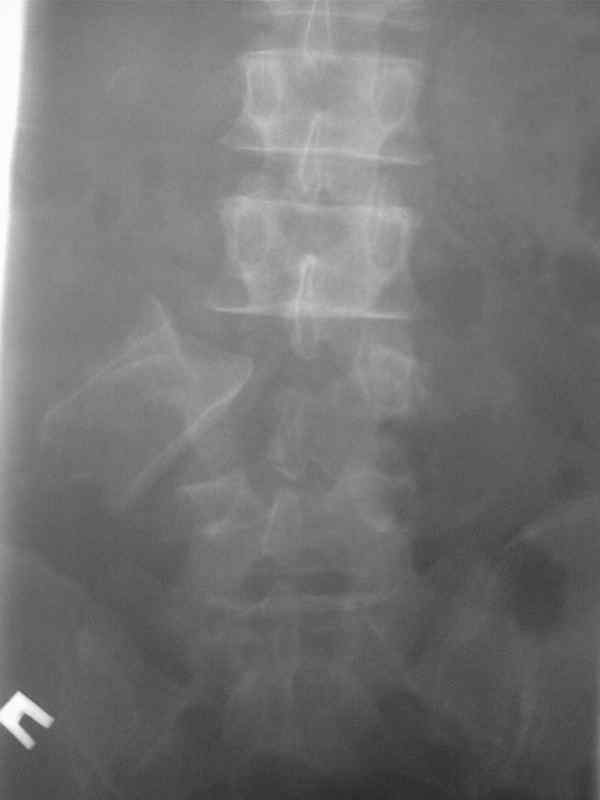

Уникальный снимок! Такое впечатление, что тело оторвалось от ножек и при этом дужка вроде, как и цела.

При этой картине удивительно еще то, что у нее нет никаких двигательных и тазовых нарушей.. Жалобы только на боли в спине. Движения и чувствительность в полном объеме. Никаких повреждений сосудистых магистралей также нет. Только изолированный перелом L5 со смещением тела позвонка в мягих тканях (забрюшинном пространстве). Остистый отросток на месте.